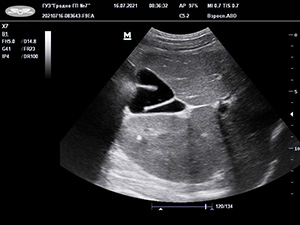

Рисунок. S-образные формы желчного пузыря. Результаты УЗИ.